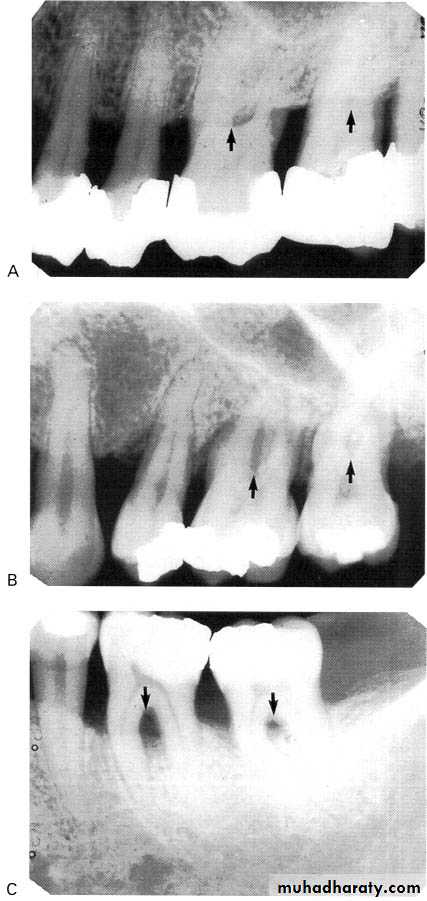

3.Furcation involvements:

Bone loss in the furcation area of the roots which is evidence of advanced disease in multirooted

teeth.

Initially seen as widening of the PL space at the crest of

the furcation . As lesion progresses, the bone

loss progresses apically.

Mild/moderate/sever.

• Severity: classified to

Mild bone loss: crestal changes (The anterior regions show blunting of the alveolar crests and slight loss of alveolar bone height.Posteriorly show loss of the normally sharp angle between the lamina dura and alveolar crest).

• Moderate bone loss: bone loss of 10-33%.

• Severe bone loss: bone loss of 33% or more.

A:moderate,B:sever.